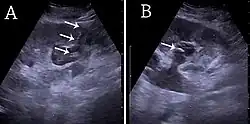

- ↑ Content initially copied from: Hansen KL, Nielsen MB, Ewertsen C (December 2015). "Ultrasonography of the Kidney: A Pictorial Review". Diagnostics. 6 (1): 2. doi:10.3390/diagnostics6010002. PMC 4808817. PMID 26838799. (CC-BY 4.0)